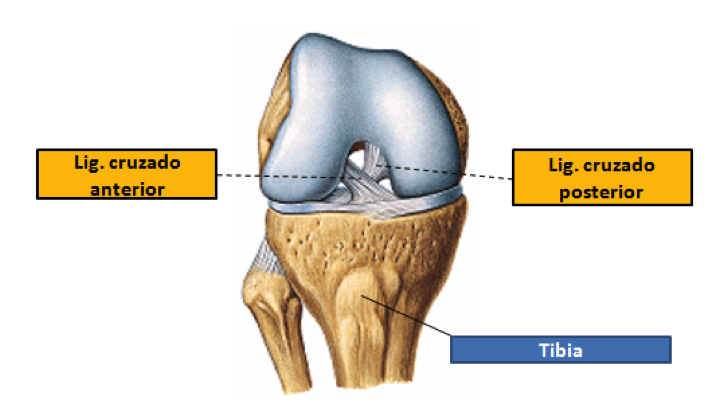

2. Visión interna de la rodilla En una visión interna de la articulación se pueden observar, principalmente, dos ligamentos muy importantes: el ligamento cruzado anterior y el ligamento cruzado posterior.